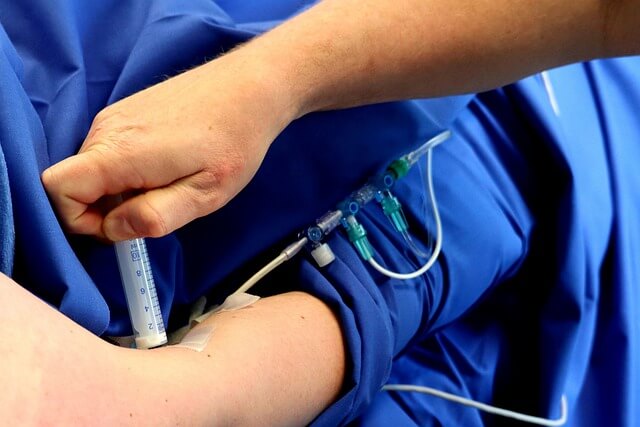

| 흉강천자 | 바늘을 이용해 흉막삼출액을 제거하여 호흡 개선 | 일시적인 해결책 |